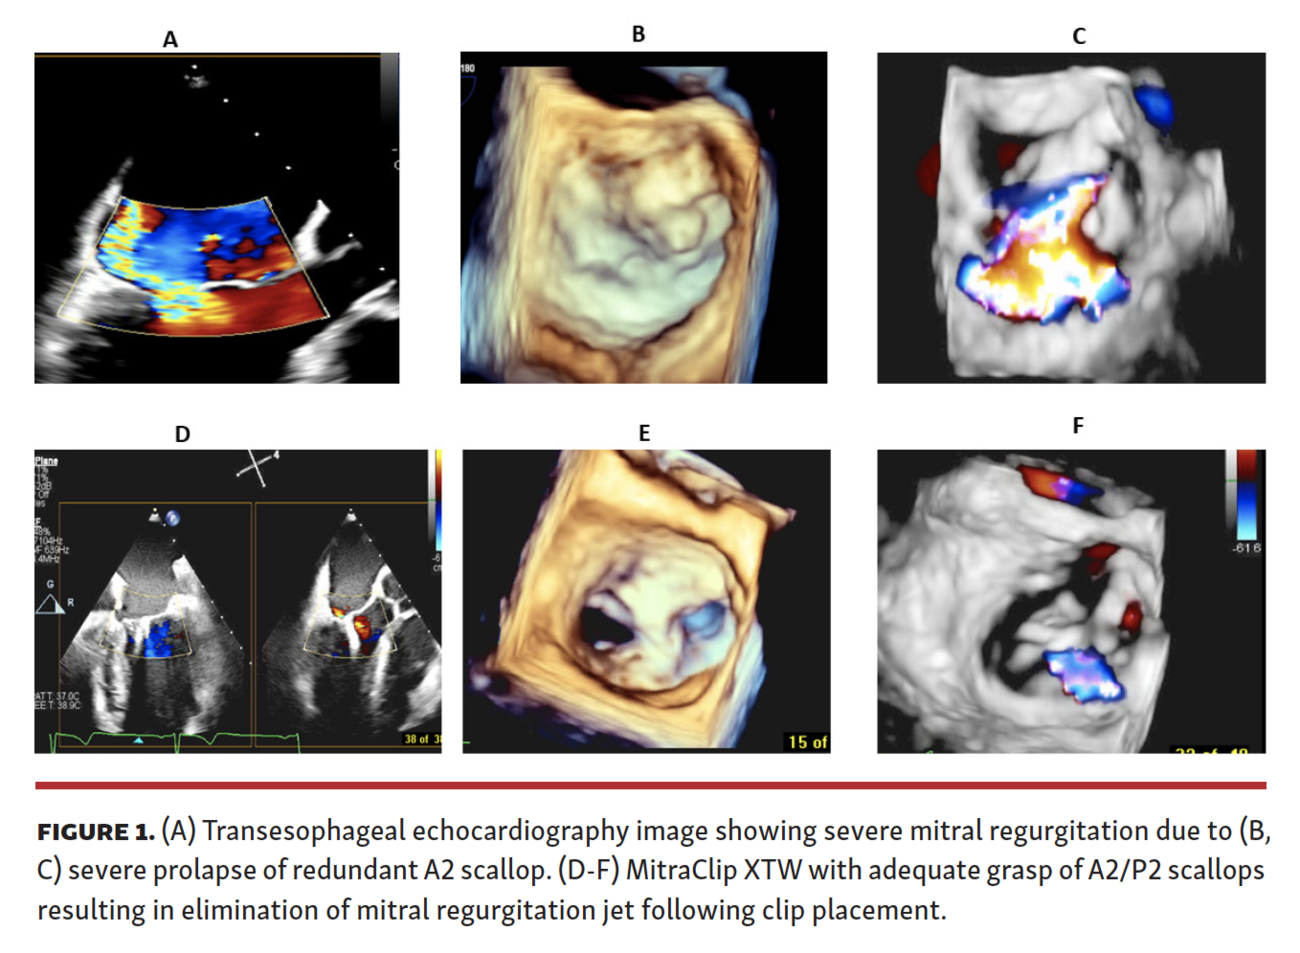

Intraoperative transesophageal echocardiography (TEE) demonstrated anterior mitral leaflet cleft and severe MR. MR jet was mostly from A2 and P2 at the vicinity of the anterior cleft (Figure 1A, Video Series). We grasped the A2 and P2 segments as close as possible to the cleft. A MitraClip XTW G4 device was placed on the A2 and P2 immediately adjacent to the cleft (Video Series), resulting in reduction of severe MR to mild MR (Figures 1B and 1C and Video Series). The mean gradient across the mitral valve was 5 mm Hg at a heart rate of 62 beats/min post clip deployment. The patient was extubated and had an uneventful recovery. She was discharged on postprocedure day 1. At 3-week follow-up exam, the patient had complete resolution of her dyspnea and orthopnea with significant improvement in exercise capacity.